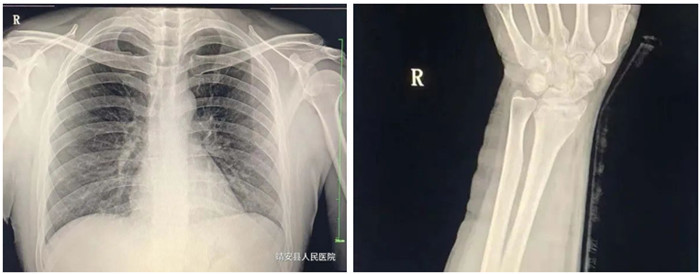

動態DR的常規攝影

2.脊柱、四肢骨骼及關節

適應癥:骨齡檢查、先天性發育異常、骨缺血性壞死;骨質疏松、骨髓炎、骨腫瘤、骨關節創傷、骨關節結核、骨關節炎性病變、軟組織病變等疾病。

3.胸部

適應癥:氣管支氣管病(支氣管結石及異物等);肺部病變(先天性發育異常、炎癥、結核、腫瘤等);縱膈病變(氣腫、血腫、腫瘤與囊腫等)。

動態DR攝影

動態DR影像

普愛醫療PLX8500D數字化醫用X射線攝影系統(動態DR)具有動態、靜態圖像采集兩種攝影方式。17*17動態大平板,900W高清像素,可以更有效覆蓋檢查范圍、降低檢查所需時間和曝光,從而確保提升影像檢查效率,有效避免廢片、漏診、誤診、二次拍攝、多次重復曝光等不良隱患情況的發生。采用超寬34寸液晶顯示器,解放雙屏雙工作站的束搏,實現采集圖像和回放圖像并列顯示,使臨床圖像效果對比更直觀,操作更方便快捷。